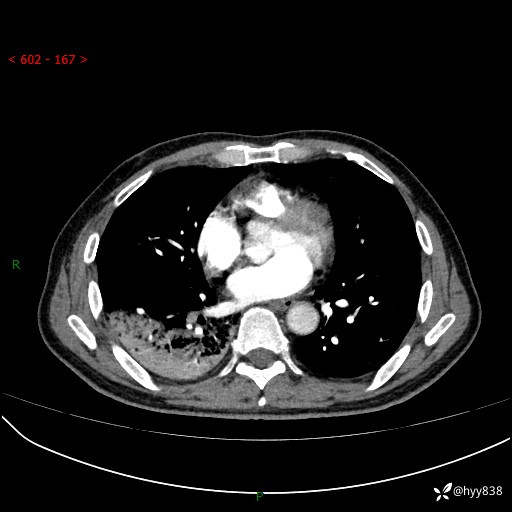

63岁/男,发热5余天。精彩好病例,“大叶性肺炎”,等你来诊---结果公布~

【患者信息】:63岁/男

【主诉】:发热5余天

【现病史及既往史】:患者5余天无明显诱因出现畏寒寒战发热,最高体温39.5℃,发热无明显昼夜规律,伴全身乏力、头晕,无头痛、无咳嗽咳痰、无胸痛咯血、无气短、无腹痛腹泻、无尿频尿急尿痛等不适,于当地市第五人民医院就诊,予以抗感染等治疗(具体不详)后发热无明显好转,1天前查胸部CT提示右下肺感染,为求进一步诊治,门诊以“社区获得性肺炎”收治入院; 起病以来,患者精神、食欲一般,睡眠可,大小便正常,体力体重较前无明显变化。

【检查】:胸部CT增强